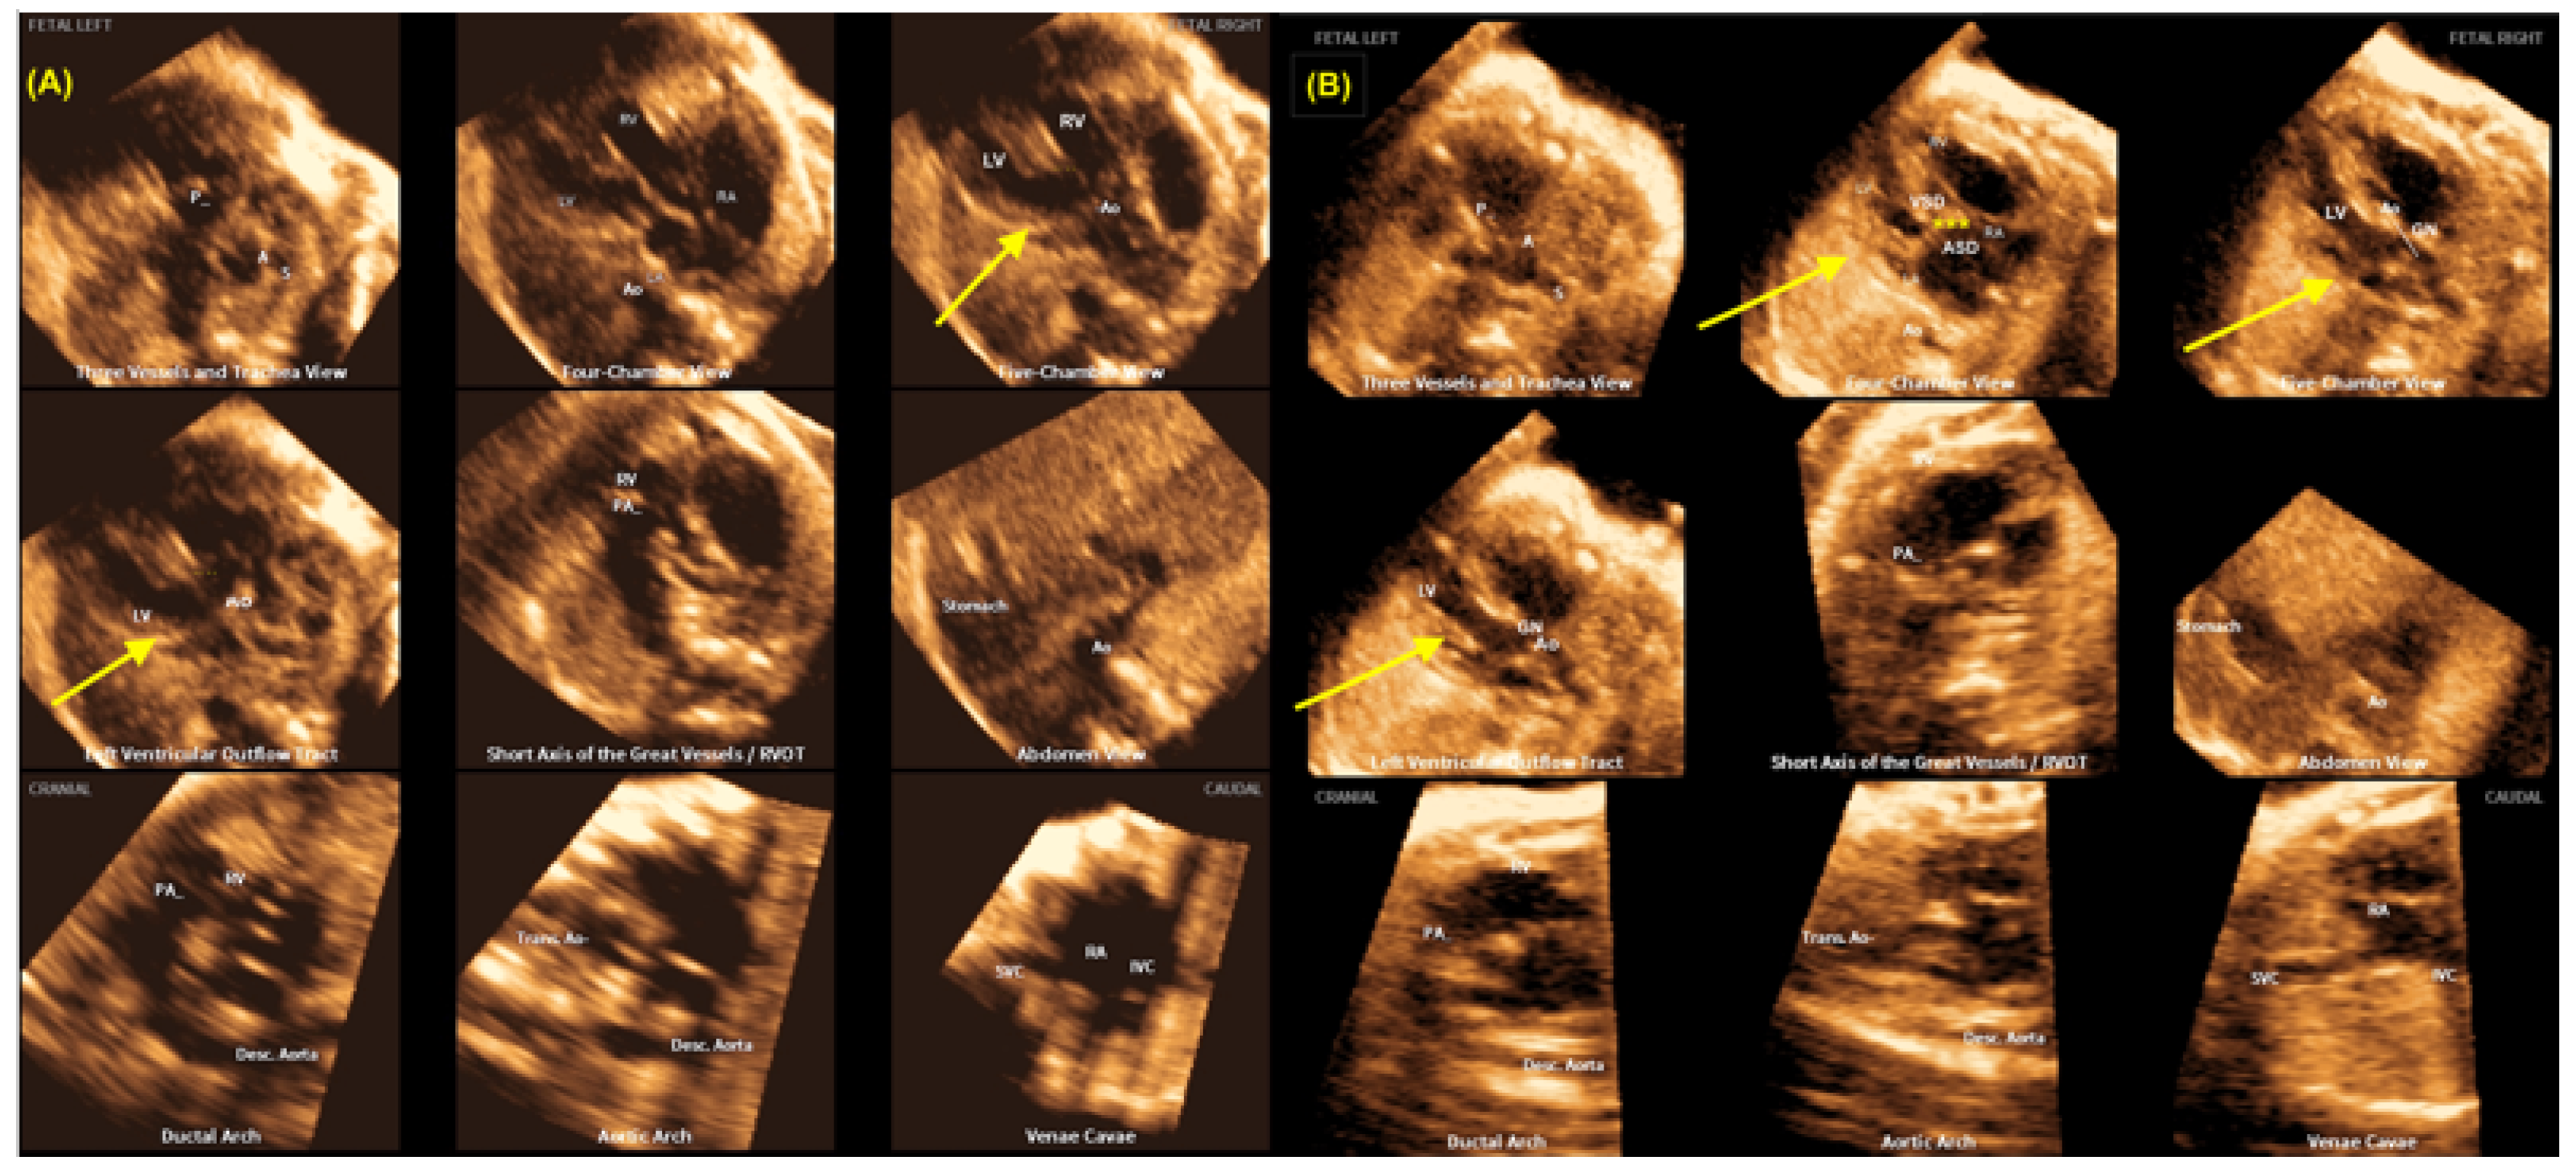

- Yeo L, Romero R. Fetal Intelligent Navigation Echocardiography (FINE): A Novel Method for Rapid, Simple, and Automatic Examination of the Fetal Heart. Ultrasound Obstet Gynecol. 2013, 42, 268–284.

- Carrillo MC, Rolo LC, Tonni G, Araujo Júnior E. Evaluation of the quality of standard fetal heart views using the FAST, STAR and FINE four-dimensional ultrasound techniques in congenital heart disease screening. Echocardiography. 2020, 37, 114–123.

- Yeo L, Romero R. Color and power Doppler combined with Fetal Intelligent Navigation Echocardiography (FINE) to evaluate the fetal heart. Ultrasound Obstet Gynecol. 2017, 50, 476–491.